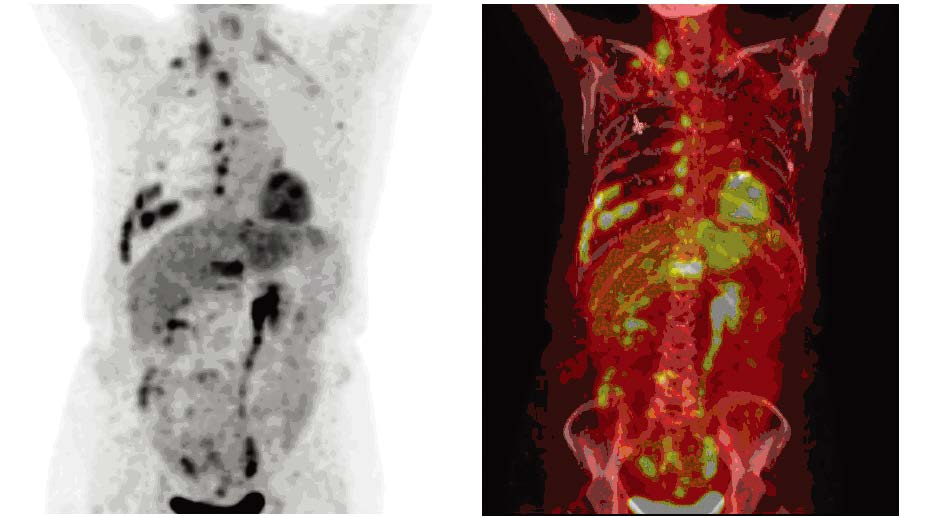

Methods18F-FDG PET/CT images of 56 breast cancer patients who underwent surgery with or without chemotherapyor radiotherapy were acquired in three days to one month after increased serum CEA and(or) CA153 werefound. Diagnoses were made by the consistent comment of two or more doctors after three experiencednuclear medicine doctors reviewed the images retrospectively and independently. And the gold standard ofdiagnoses were the results of either pathology or one-year follow-up.

ResultsOf all 56 cases, there were twocases of local recurrence, 30 cases of metastasis, 14 cases without recurrence and 10 cases of second primarytumor. 18F-FDG PET/CT imaging was positive in 41 cases (one false positive case), negative in 15 cases (twofalse negative cases). The diagnostic efficiency of 18F-FDG PET/CT were: sensitivity 95.24%, specificity92.86%, accuracy 94.64%, false negative rate 4.76%, false positive rate 7.14%, positive predictive value(PPV) 97.56%, and negative predictive value (NPV) 86.67%. The PPV of increased CEA alone, increasedCA153 alone and their combination were 57.14%, 90.91% and 94.12%, respectively (χ2=10.430, P=0.005).

Conclusion18F-FDG PET/CT can be used to identify or rule out the recurrence and metastasis in breastcancer patients with increased serum CA153 and(or) CEA after treatment, with high diagnostic efficiency andgood clinical application value. And it can also suggest the second primary tumor.